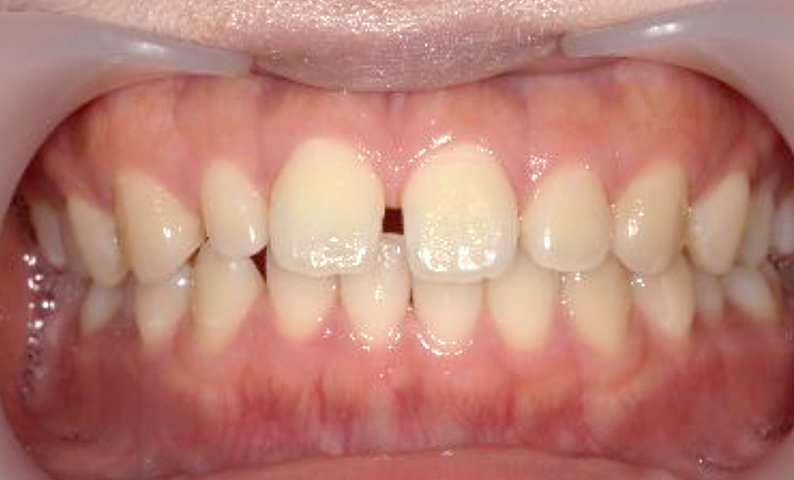

| 治療前 | 治療後 |

|---|---|

|